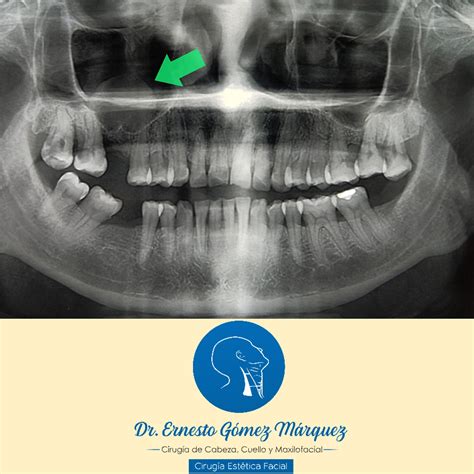

Caso 638, varón, 29 años Mucocele en el seno maxilar izquierdo y osteoma en el complejo etmoidal del lado izquierdo En la visita a nuestra clínica el paciente refirió un dolor en la zona del seno maxilar izquierdo. En la radiografía panorámica practicada se observó un seno maxilar izquierdo completamente velado y un engrosamiento de la mucosa basal en el seno maxilar derecho (fig. 1). Se identificaron además diversos dientes que requerían tratamiento odontológico.